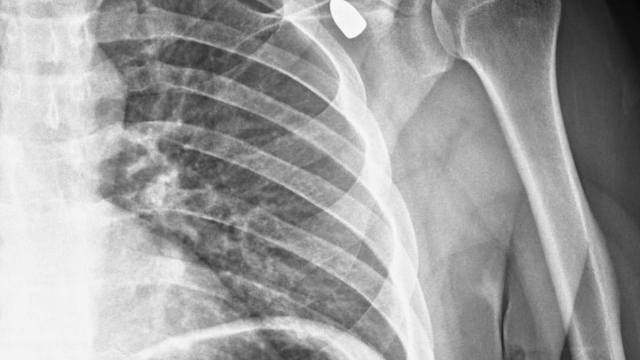

Konya'nın Akşehir ilçesinde altı yıl önce bir okul müdürünün omzuna isabet eden yorgun mermi tıbbi müdahaleyle çıkarıldı.

Okul müdürü Celal Şenyiğit, Adsız Mahallesi'ndeki çay ocağında, altı yıl önce omzuna isabet eden yorgun mermiyle yaralandı.

Hareket kaybı riski nedeniyle çıkarılamayan mermi, zamanla Şenyiğit'in koltuk altına ilerledi. Ağrı ve sertlik şikayetiyle Akşehir Devlet Hastanesine başvuran Şenyiğit'in koltuk altındaki kitlenin, omzuna saplanan yorgun mermi olduğu tespit edildi.

Mermi, gerçekleştirilen operasyonla çıkarıldı.